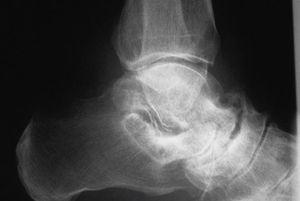

Las principales pruebas complementarias de diagnóstico son las proyecciones radiográficas en carga, donde se demuestra una disminución del ángulo de Moreau-Costa-Bartani (fig. 5) y del ángulo de divergencia astragalocalcáneo. La radiografía de perfil permite además observar la zona de inflexión del arco plantar (fig. 5). Según la huella plantar, clasificamos este pie en precavo o cavo de primer o segundo grados (fig. 6). El precavo, o cavo dinámico, es la situación observable en el niño con una desnivelación reductible y una huella plantar prácticamente normal. El cavo de primer grado es secundario a una desnivelación parcialmente fijada, con reducción de la banda externa de la huella (inferior a un tercio de la amplitud del antepié), mientras que en el cavo de segundo grado, al ser la desnivelación más importante, se marca tan sólo la huella de los pilares anterior y posterior.

Figura 5. Pie cavo anterior: retropié normal, antepié verticalizado (A), y pie cavo posterior: retropié muy verticalizado (B). Ángulo de Moreau-Costa-Bartani reducido.